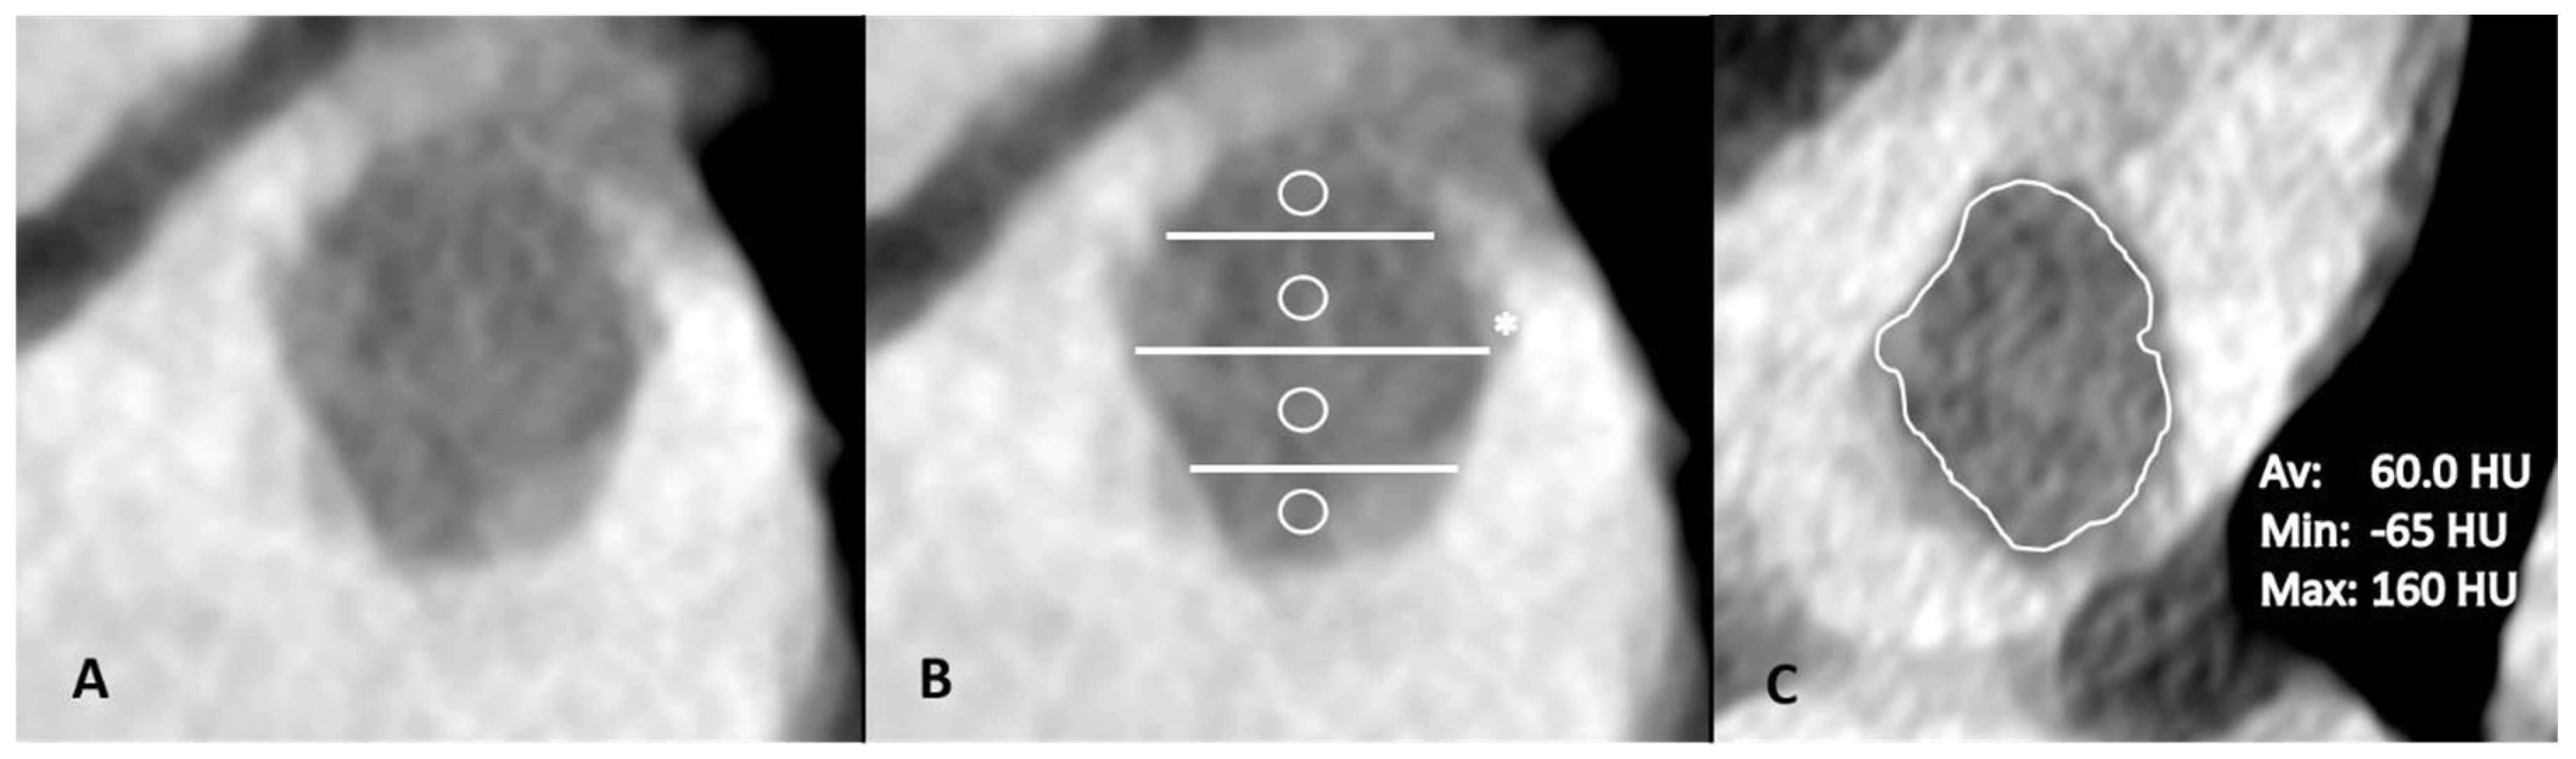

- Hur, J.; Kim, Y.J.; Lee, H.-J.; Nam, J.E.; Hong, Y.J.; Kim, H.Y.; Lee, J.W.; Choi, B.W. Cardioembolic stroke: Dual-energy cardiac CT for differentiation of left atrial appendage thrombus and circulatory stasis. Radiology 2012, 263, 688–695. [Google Scholar] [CrossRef] [PubMed]

- Kirchhof, K.; Welzel, T.; Mecke, C.; Zoubaa, S.; Sartor, K. Differentiation of white, mixed, and red thrombi: Value of CT in estimation of the prognosis of thrombolysis phantom study. Radiology 2003, 228, 126–130. [Google Scholar] [CrossRef]